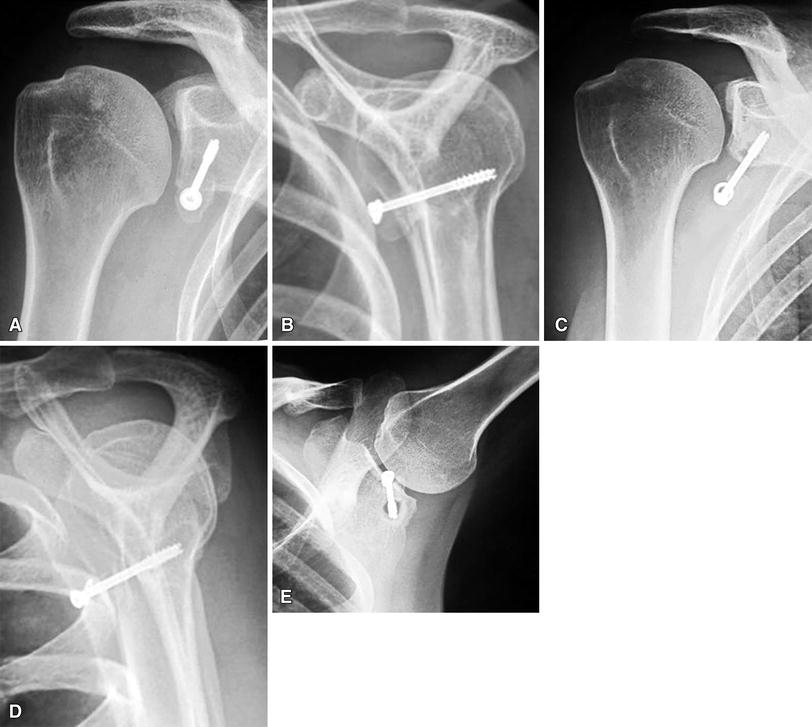

Postoperative radiograph after the Bristow Latarjet repair (at 43... Download Scientific Diagram

Postoperative radiograph after the Bristow Latarjet repair (at 43... Download Scientific Diagram Bristow Repair the bristow procedure, and its variants, describes transfer of the coracoid process through the subscapularis tendon as. the current method of modified arthroscopic bristow procedure with screw fixation without subscapularis split reduces surgical time, reduces the risk of nerve damage consequences, and is simple to apply. the bristow procedure, and its variants, describes transfer of the coracoid. Bristow Repair.